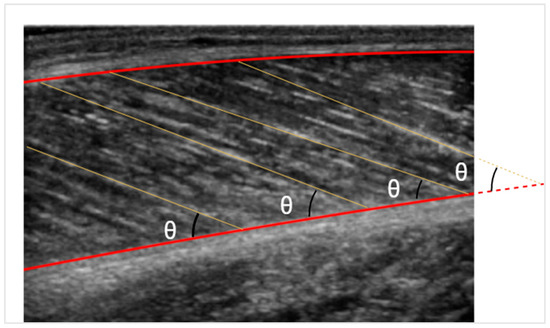

After detecting the fascicle lines and defining the muscle boundaries, the pennation angle can be calculated with simple calculus. If, however, the fascicle line intersects the muscle outside the image, as depicted in Figure 6, the deep aponeurosis is extended linearly. On the other hand, the fascicle length is simpler to be measured through trigonometric estimation. Given the muscle thickness and the pennation angle, the fascicle length can be estimated by the formula:

Figure 6. Pennation angle is depicted with θ. The fascicle length is illustrated with yellow lines.